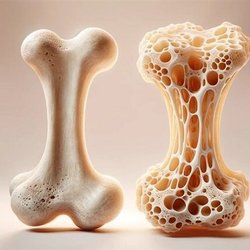

پوکی استخوان در نیمی از زنان بالای ۵۰ سال

مدیرکل دفتر مدیریت بیماریهای غیرواگیر وزارت بهداشت با بیان اینکه از هر دو زن بالای ۵۰ سال، یک نفر به پوکی استخوان مبتلاست، گفت: اگرچه بخشی از عوامل پوکی استخوان مانند ژنتیک، نژاد و جنس قابل تغییر نیست، اما با اصلاح سبک زندگی میتوان روند بیماری را به تأخیر انداخت.